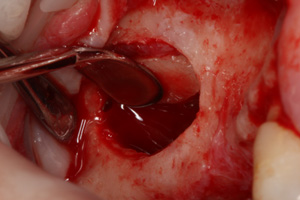

W metodzie z wypreparowaniem okna bocznego jesteśmy w stanie uzyskać nawet do 10mm nowej, świeżo utkanej tkanki kostnej, jednak przed wprowadzeniem implantu, wymagane jest odczekanie około 6-9 miesięcy w celu uzyskania przebudowanej, uformowanej nowej kości zdolnej do przyjęcia wszczepu. Niekiedy istnieje możliwość jednoczasowej implantacji wraz z zabiegiem podniesienia dna zatoki przy korzystnych relacjach ilości własnej kości do kości nowo tworzonej po zabiegu podniesienia dna zatoki. Postępowanie takie pozwala przyspieszyć zakończenie leczenia o okres późniejszego oczekiwania na osteointegrację implantu.

W każdej z metod, po odwarstwieniu błony Schneidera (błony śluzowej wyścielającej ściany zatoki), w wytworzoną przestrzeń wprowadzany jest materiał kościozastępczy będący zrębem dla powstawania nowej tkanki kostnej.